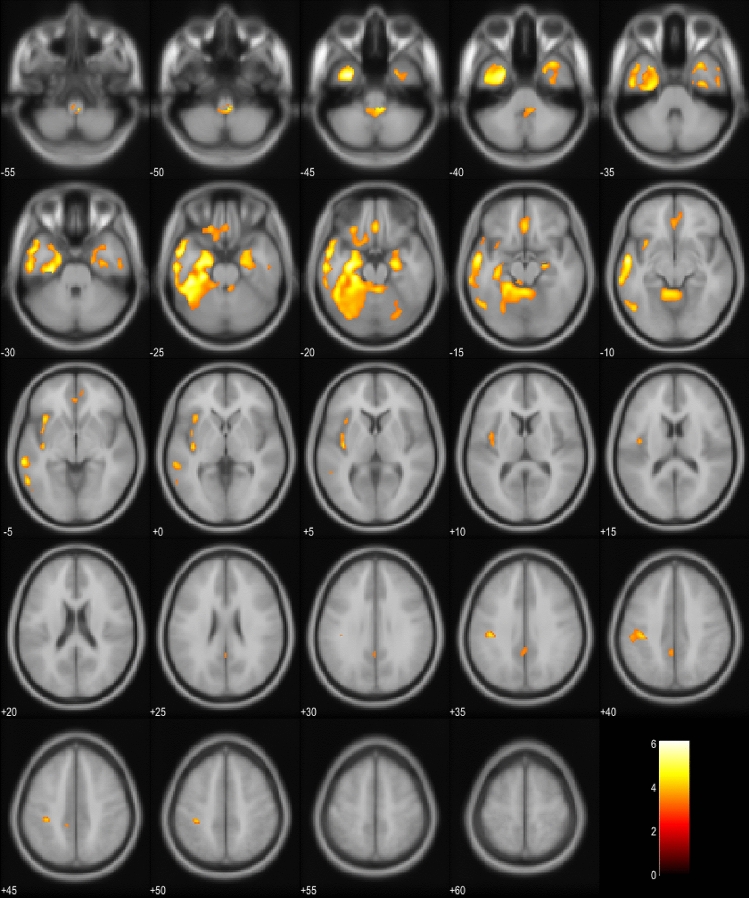

18FDG-PET scans of the EP + patients were compared to the scans of the EP- patients in the whole cohort and also in the subgroup including only bvFTD patients (Fig. 1a, b). In the whole cohort, EP + patients showed significant hypometabolism predominantly in the left hemisphere in the temporal and medial frontal lobes. In the bvFTD subgroup, similar results were obtained in the EP + patients with hypometabolism detected mostly in the left temporal lobe. Also, the SCP and the frontal lobes showed hypometabolism. Comparison between EP + bvFTD patients and patients with PSP or CBD indicated that the bvFTD patients specifically showed hypometabolism in cerebellar lingula and SCP (Fig. 1c). No differences were observed in the cortical regions.